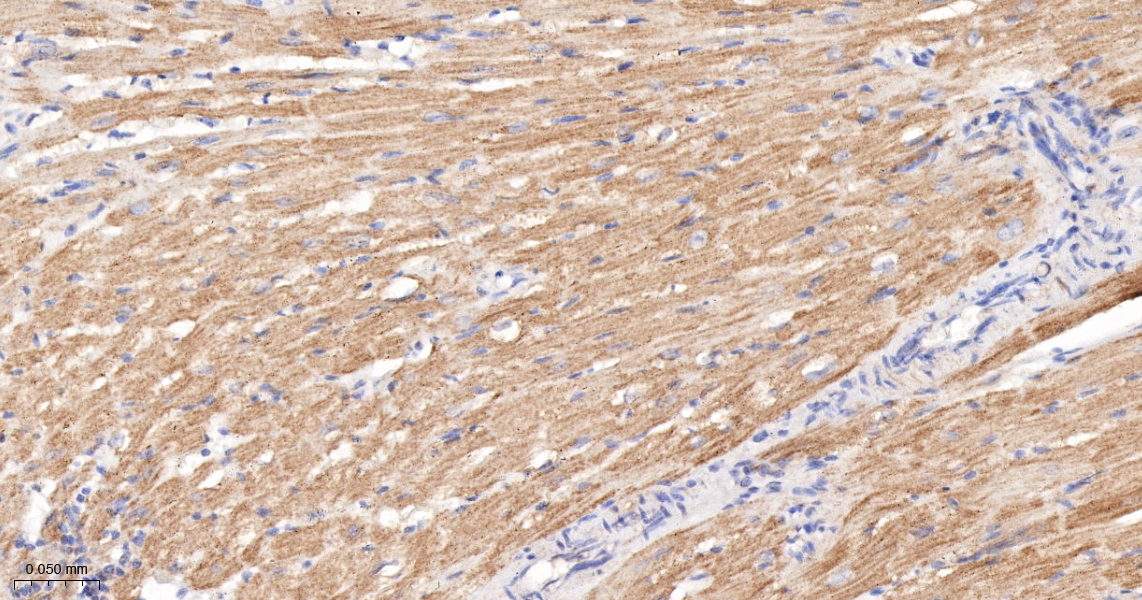

phospho-RAF1 (Ser259) Recombinant Antibody

Product Name phospho-RAF1 (Ser259) Recombinant Antibody

Applications WB, IHC-P, IHC-F, IF

Reactivity Human, Mouse, Rat

IHC-P 1:200-400